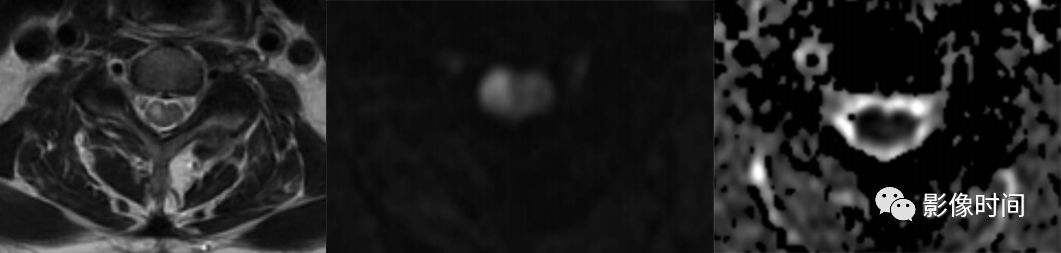

脊髓梗死(spinal infarction),各种原因(比如动脉夹层、椎体术后、纤维软骨栓塞等等)导致的脊髓供血动脉缺血,脊髓前动脉最多见

前 2/3 脊髓(脊髓前动脉);双侧灰质前角(脊髓前动脉);后索(脊髓后动脉)

T2WI 高信号病灶,DWI 呈高信号,ADC 呈低信号

轴位「鹰眼征」

-

脊髓前动脉梗死导致双侧灰质前角梗死(鹰眼征),矢状位呈线样,DWI 提示细胞毒性水肿

脊髓前动脉梗死导致脊髓前 2/3 梗死,DWI 提示细胞毒性水肿

脊髓后动脉梗死导致脊髓后索梗死,DWI 提示细胞毒性水肿